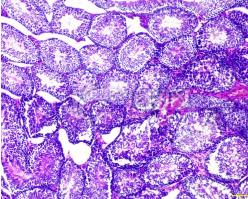

石蜡切片

其优点是组织结构保存良好,在病理和回顾性研究中有较大的实用价值,能切连续薄片,组织结构清晰,抗原定位准确。用于免疫组化技术的石蜡切片制备与常规制片略有不同:①脱水、透明等过程应在4℃。C下进行,以尽量减少组织抗原的损失。②组织块大小应限于2cm×1.5cm×0.2cm,使组织充分脱水、透明、浸蜡。③浸蜡、包埋过程中,石蜡应保持在60℃以下,以溶点低的软蜡最好(即低温石蜡包埋)。

石蜡切片为常规制片技术,切片机多为轮转式,切片厚度2~7μm,应用范围广,不影响抗体的穿透性,染色均匀一致。由于甲醛固定、有机熔剂和包埋剂对组抗原有一定的损害及遮蔽,使抗原特征发生改变。有人报告经蛋白酶消化,可以改善光镜免疫组化染色强度,常用的有胰蛋白酶、链霉蛋白酶及胃蛋白酶等消化法。石蜡切片应入37℃恒温箱过夜,这样烤片可减少染色中脱片现象。切片如需长期贮存,可存放于4℃冰箱内备用。